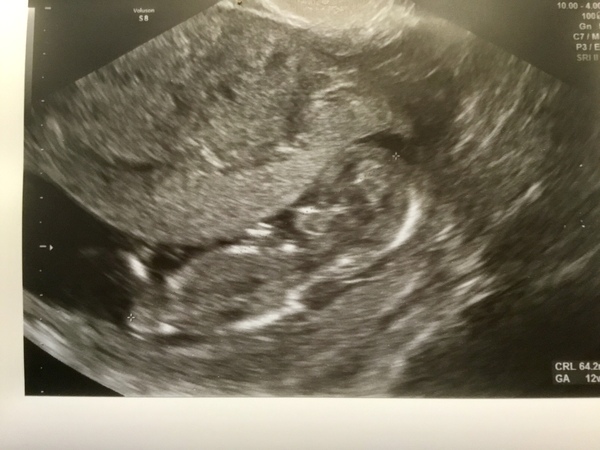

I looked at some nub theory info this morning and then my scan photo and I’m a bit in shock that I think from looking at the nub it’s a boy. I guess I always saw myself with two girls but I don’t know why. Please don’t think that I’m disappointed, I’m just trying to get my head around it. Attaching picture to see if you agree

June 2019 Thread 4 - sliding towards 2nd trimester

@reastie I saw your post and realised I hadn't even looked for a nub on my scans. I really don't know what I'm looking for! Do you think boy because the white bit sticks up? What do you think of mine?